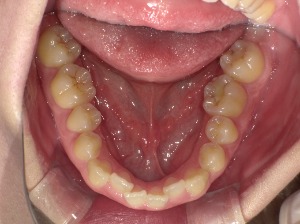

特に多いのが下の前歯のガタつき。

これらが重なり、前歯が押し合って乱れることがあります。

✔ 下の前歯が重なってきた